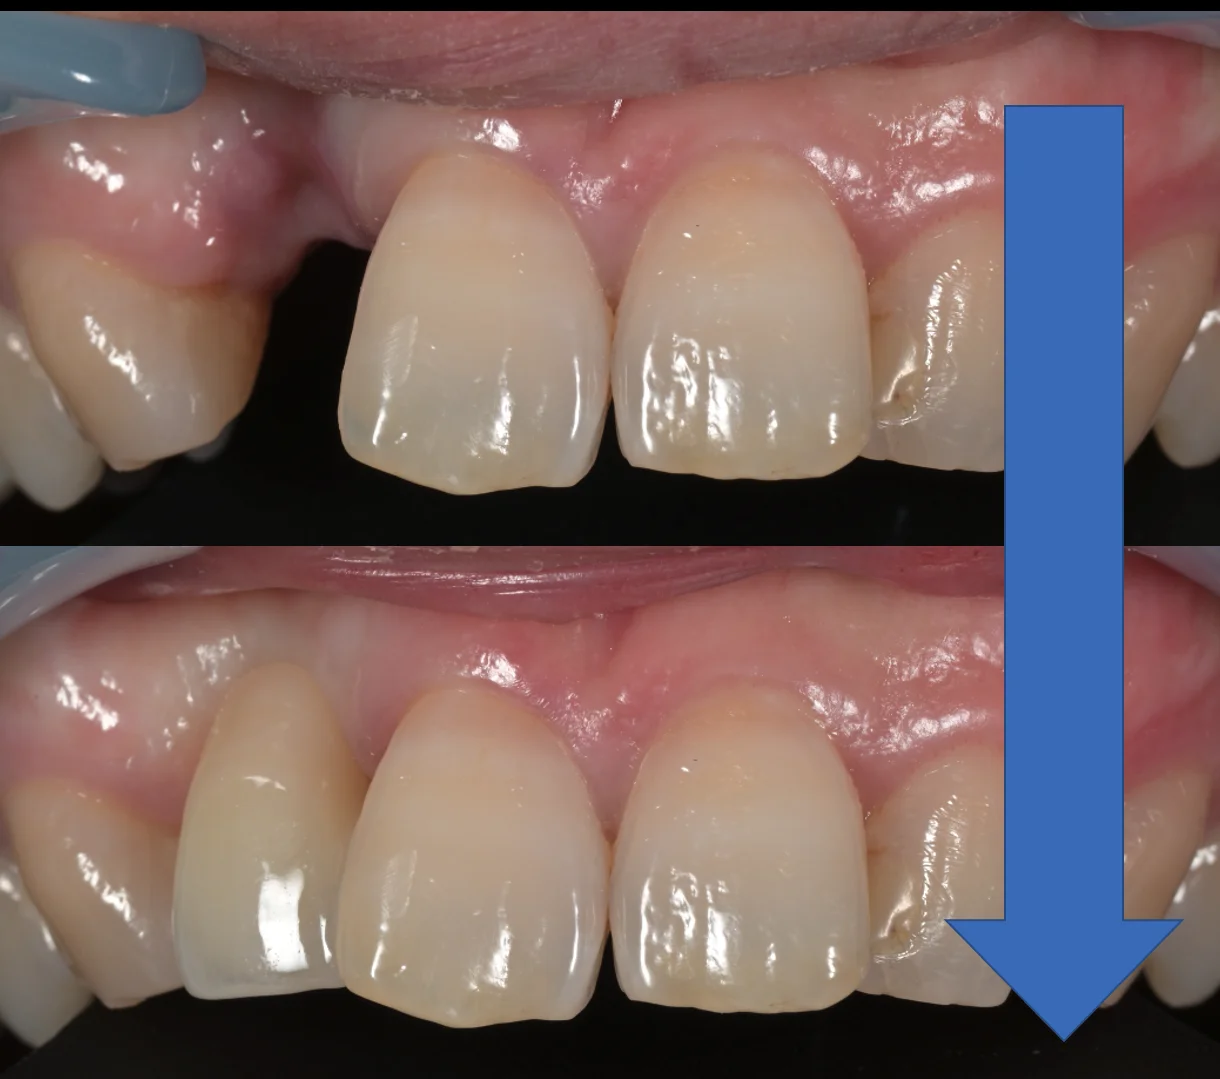

正面からの術前術後です。